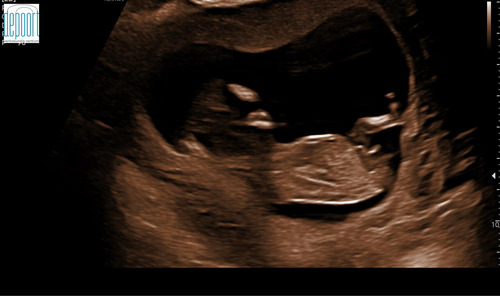

Als je een mooie foto hebt(dat is deze ook) en kindje ligt er goed voor kan je hem vrijwel altijd goed beoordelen is mijn ervaring.

Onder de navelstreng zie je inderdaad dat de nub naar boven wijst. Plaats je foto ook eens in het algemene nub theorie topic :) weet zeker dat je alleen 馃挋馃挋馃挋 krijgt 馃グ